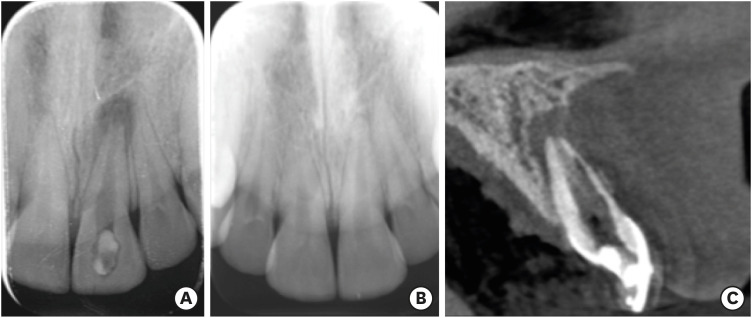

A 20-year-old woman with a history of root canal treatment of the upper maxillary (left) central incisor was referred to our department from a private clinic. The root canal treatment had been initiated 4 months prior but could not be finished. A clinical examination revealed a temporary filling on the palatal surface. The coronal part of the tooth was discolored, and multiple visible cracks were present on the buccal surface (Figure 1). The tooth was asymptomatic; the mobility was normal, and the probing depth at all sites was ≤ 3 mm. A periapical radiograph revealed a lesion around the apex and an enlarged and clearly irregular root canal (Figure 2A). When specifically asked, the patient denied knowledge of any previous dental trauma. Upon checking the electronic documentation of the faculty of the institution, we found that the patient had visited the department 2 years prior for other reasons, and X-rays were taken at that appointment. From a comparison of the periapical X-rays, it was clear that something must have happened since her last visit (Figure 2B). After gaining her confidence, the patient and her mother admitted that the patient had suffered from domestic abuse at the hands of her boyfriend, but that had been taken care of by the police. At this point, a small-field-of-view high-resolution cone-beam computed tomography (CBCT) scan was taken to investigate the extent and irregularity of the lesion. The scan confirmed the presence of a periapical lesion, which had destroyed most of the buccal bony wall around the root. The scan also showed massive internal resorption inside the root canal (Figure 2C). The patient was informed of the findings and the poor prognosis of the tooth, but since she desperately wanted to keep her tooth, she provided consent for endodontic treatment, which was initialized at a later appointment. The patient was also informed that due to the irregular nature and more pronounced buccolingual extent of the resorptive lesion and the massive destruction of the buccal bony plate, which cannot be seen or monitored on periapical X-rays, it would be beneficial to control the steps of the treatment and perform the monitoring via CBCT scans. The patient was informed of the extra radiation exposure resulting from the CBCT scans, but she insisted on undergoing scans instead of periapical X-rays when deemed beneficial by the clinicians.

Figure 2

Images of the patient's tooth upon presentation and 2 years prior. (A) X-ray image upon presentation. (B) X-ray of the same tooth from 2 years prior. (C) Cone-beam computed tomography image of the tooth upon presentation.